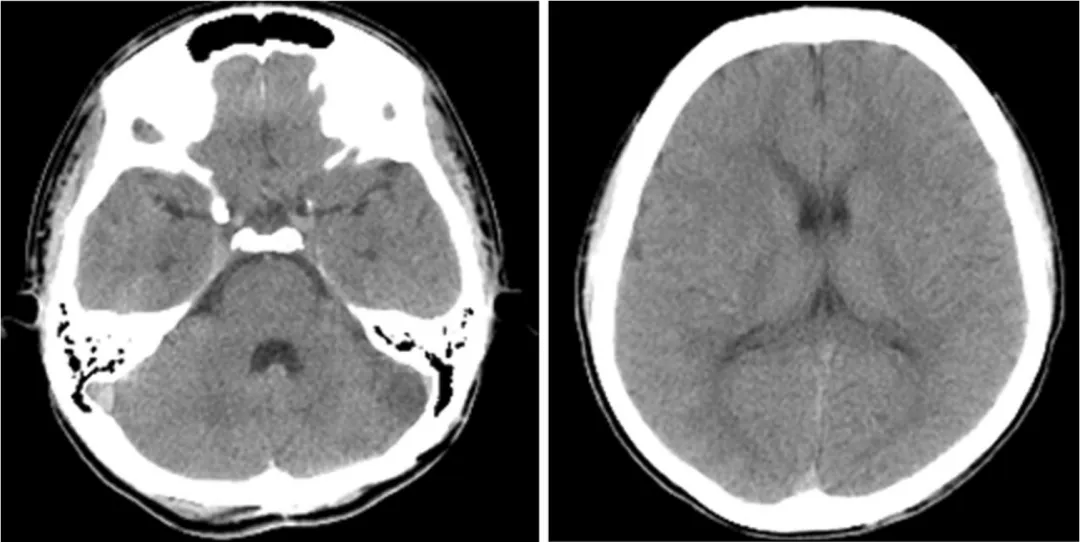

术后CT,无明显缺血性病变或脑积水

术后影像结果让人欣慰:头颅CT没有发现新发缺血性病灶,血管造影显示左侧小脑前下动脉完全闭塞,动脉瘤和动静脉瘘被彻底清除,没有残留。